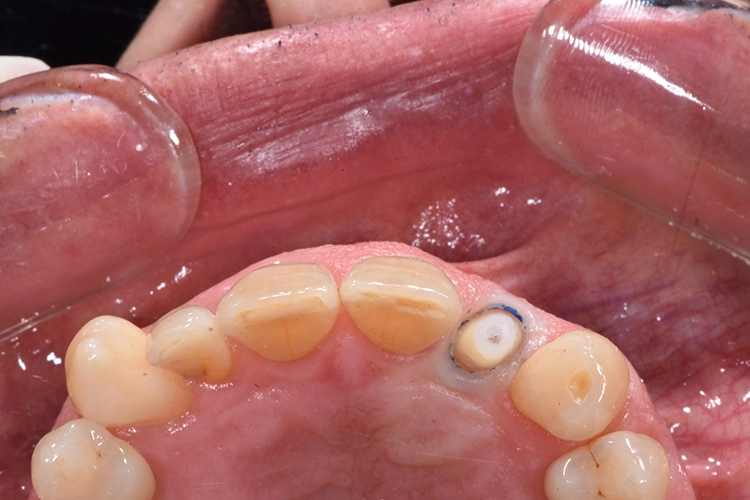

Anschließend wurde der durch die externe Resorption stark angegriffene Wurzelrest schonend entfernt. Bei der Sofortimplantation kommt es auf den Erhalt der lokalen knöchernen Bedeckung an.

Die Alveole wird von Granulationsgewebe gesäubert und direkt postoperativ durch ein Kleinröntgen auf Wurzelreste kontrolliert. Die Aufbereitung des Implantatbettes und die Implantatinsertion erfolgt im apikalen Bereich tendenziell eher palatinal. Im Bereich der Implantatschulter wurde ein Abstand von 2,5 mm zur vestibulären Lamelle eingehalten.

Aufgrund der Angulation der Implantate im Frontzahnbereich steht man mit einem verschraubten Provisorium oftmals vor dem Problem des vestibulär durchtretenden Schraubenkanals. Dieses Problem lässt sich mit dem iSy System elegant umgehen.

Für die Herstellung des Provisoriums wird die Zahnkrone zunächst von Granulationsgewebe befreit, anschließend mithilfe rotierender Instrumente und dem Sandstrahlgerät gereinigt und für die adhäsive Verbindung mit dem PEEK-Aufbau vorbereitet. Intraoral wird die Zahnkrone mit dem provisorischen Abutment verklebt.

Die erste Verbindung dient ausschließlich der dreidimensionalen Fixierung in Relation zum Abutment. Die weitere Ausarbeitung der Krone erfolgt extraoral, wobei auf die Gestaltung eines physiologischen Emergenzprofils geachtet werden muss. Anschließend wird das Provisorium einfach auf die Implantat-Basis geklickt, das Bild zeigt die Situation unmittelbar nach der Implantation (Abb. 23-28).